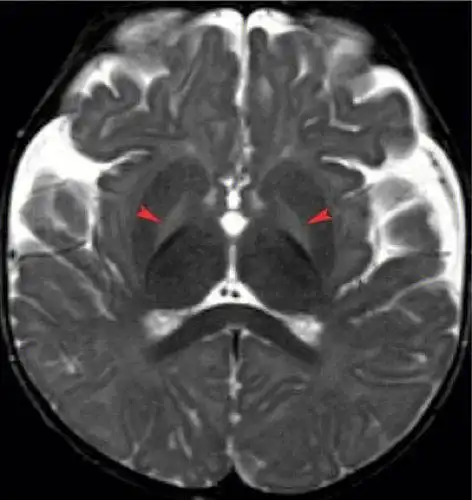

胆红素脑病的mri诊断

头颅mri胆红素脑病的特征性异常信号

胆红素脑病